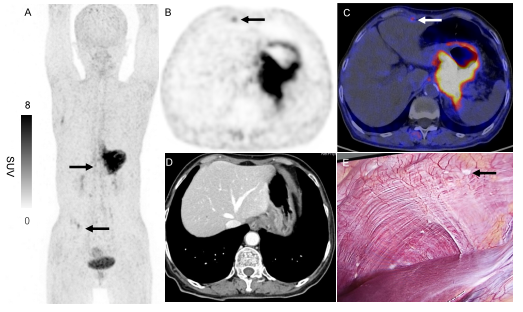

2例典型病例共同证明了68Ga-FAPI-04 PET/CT在检查进展期胃癌OPM中的独特价值,见图1和图2。

图1 1例71岁女性胃体低分化腺癌患者接受68Ga-FAPI-04 PET/CT检查显示:右上腹及右下腹象限存在多处病灶(A:箭头所示;SUV最大值为4.17)。轴位图像精确定位上腹部病灶位于右膈下间隙(B、C,箭头所示)。值得注意的是,增强CT在相应位置未见异常(D),但后续术前腹腔镜检查在膈肌表面发现微小种植灶(E:箭头所示),证实存在OPM